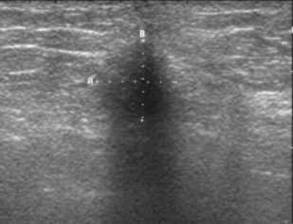

ECOGRAFIA MAMARA

Sanul a fost unul din primele organe examinate ultrasonografic dar importanta imagisticii ultrasonice a bolilor sanului ramane inca subevaluata. Imaginile ecografice aduc elemente extrem de valabile pentru afirmarea afectiunilor mamare si aceasta informatie poate fi suverana pentru a permite o conduita corecta vis a vis de paciente. In cursul ultimilor ani, obtinerea de imagini de inalta rezolutie a contribuit, de o maniera semnificativa, la acceptarea tehnicilor ecografice

SEMIOLOGIA ECOGRAFICA

Semiologia ecografica este ansamblul semnelor sau a semnalelor care sunt necesare si suficiente pentru a stabili diagnosticul de tumora maligna/ benigna a sanului.

Patru tipuri de semnale ecografice pot fi descrise evocand, in diverse grade, diagnosticul de malignitate:

1) SEMNAL FIBROS

lacuna hipoecogena, nestructurata, ' bizara “

Disociatie eco-clinica ecostructura este neomogena si / sau heterogena

conturul este neregulat, difuz, infiltrativ; uneori conturul este destul de regulat, rar are o coroana hiperecogena (10 %);

atenuarea posterioara apare doar in 30 % din cazuri;

axul mare al lacunei este vertical sau oblic orientat spre tesuturile superficiale ale glandei;

intreruperea brutala a structurilor tisulare mamare si / sau a lamei adipoase premamare ( comparabil cu ' eruptia unui vulcan ' );

' indicele de rezistenta “ ecoseismografia lui Kobayashi ). Lacuna maligna se deplaseaza, sub presiunea transducerului, impreuna cu structurile vecine fara a-si modifica forma si conturul;

Semnal de alarma liniile hiperecogene cu directie nemamelonara.

Orice anomalie ecografica liniara, toate imaginile hipoecogene, toate atenuarile necicatriciale, orice ingrosare a unei creste Duret, trebuie sa trezeasca atentia. Imaginea lacunara trebuie analizata in functie de marime:

Lacuna se prezinta ca o imagine hipoecogena fara perete propriu, cu contur adesea difuz, fluu, atenuat. Forma lacunei este frecvent rotunda, cu diametrul vertical superior sau egal cu diametrul orizontal. Atenuarea este frecvent slaba in spatele lacunei. Peretele posterior al lacunei este rar complet.